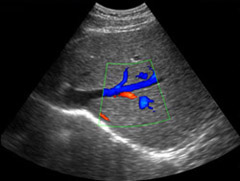

Страшная аббревиатура УЗДГ расшифровывается так: ультразвуковая допплерография сосудов. Это один из методов диагностики с помощью ультразвука, позволяющий точно определить нарушения кровообращения в сосудах, или его отсутствие. Важно, что метод этот недорогой и при этом достаточно информативный. УЗДГ применяют для исследования состояния артерий и вен, при этом величина сосуда может быть любой – от крупной вены до мелкой артериолы. С помощью УЗДГ сосудов исследуют состояние кровотока и сосудистого русла артерий и вен головы (поверхностных и внутричерепных), шеи, внутренних органов, конечностей, сосудов глаз.

УЗДГ сосудов, или, как его еще называют, ультразвуковая ангиография, выявляет состояние просвета сосуда, стенки сосуда, их извилистость, состояние клапанного аппарата вен, наличие стенозов (патологических сужений) и выпячиваний, измерить скорость кровотока, что необходимо для оценки его качества. Всю важность УЗДГ сосудов и полученной с ее помощью информации можно оценить, если вспомнить, что заболевания сердечно-сосудистой системы и их осложнения являются главной причиной смертности людей во всем мире.